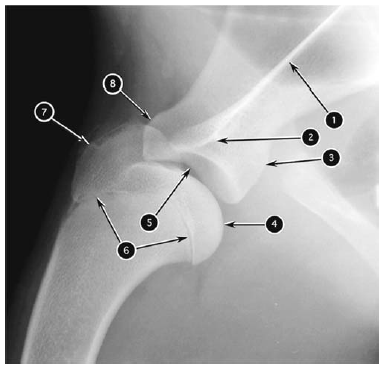

Mediolateral radiograph of canine shoulder joint

What number?

- Head of humerus

- Greater tubercle of humerus

- Proximal physis of humerus

- Supraglenoid tubercle of scapula

- Infraglenoid tubercle of scapula

- Glenoid cavity of scapula

- Acromion of scapula

- Spine of scapula

A

1. Spine of scapula

2. Acromion of scapula

3. Infraglenoid tubercle of scapula

4. Head of humerus

5. Glenoid cavity of scapula

6. Proximal physis of humerus

7. Greater tubercle of humerus

8. Supraglenoid tubercle of scapula